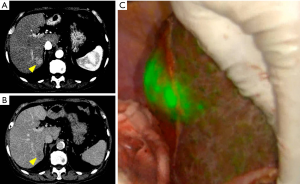

The mechanism of ICG fluorescence imaging of HCC has been elucidate by immunohistochemical staining and gene expression analysis (7,17). The optimal timing and dose of ICG administration for this use have not yet been proved. Generally, ICG (0.5 mg/kg body weight) is intravenously administered within 2 weeks before surgery in this method. ICG administration on the day before surgery in patients with decreased liver function should be avoided to reduce incidence of false-positives and background liver fluorescence. Further, in differentiated HCC, the expression levels of portal uptake transporters of ICG are well preserved, but biliary excretion disorder leads to retention of ICG in cancerous tissues (18) (Figure 1). However, in the case of poorly differentiated HCC, not only are the portal uptake transporters downregulated in cancerous tissues but the biliary excretion of ICG by surrounding non-cancerous hepatic parenchyma is also disordered, which results in rim-type fluorescence (18). It has been reported that the rim-type fluorescence signal found in patients with colorectal liver metastases is caused due to reduced bile excretion ability of the immature hepatocytes surrounding the tumor (19).

One of the disadvantages of ICG fluorescence imaging-based tumor detection is the relatively high false-positive rate. According to previous reports, out of the lesions newly detected only by fluorescence imaging of resected HCC specimens, 40–50% were non-cancerous lesions, such as regenerative nodules, atypical adenomatous hyperplasia, adenomatous hyperplasia, and bile duct proliferation (10,20). For this reason, additional resection of these lesions should be recommended only when the other diagnostic modalities (re-evaluation of preoperative images, especially MRI, palpation/visual inspection, and/or intraoperative ultrasonography) also support a possibility of malignancy. Figure 2 demonstrates a false-positive nodule detected only by intraoperative ICG fluorescent imaging. The pathological diagnosis was a large cell regenerative nodule.